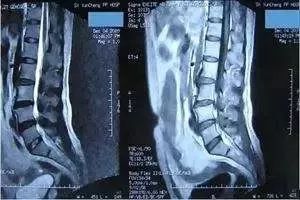

CT也是用射线穿透身体,但跟X线检查不同,现在多排螺旋CT检查是通过采集扫描范围内人体的每一个体素进行成像,说白了就是把要检查的部位划分无数体积不足一个立方毫米的微小方块,看得更细,很细微的病变也能被发现。

CT最常用在头部、胸部、腹部和脊柱疾病等方面的检查,有些四肢和骨骼问题用X线检查看不清楚时,也可以选择做CT。目前体检项目中的CT主要是胸部CT,用于早期肺癌筛查。